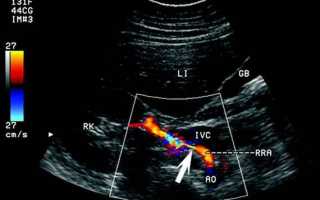

УЗДГ сосудов органов брюшной полости

При обследовании можно обнаружить дефекты строения брюшной аорты и ее ветвей, атеросклеротические изменения, врожденную двойную дугу, стеноз чревного ствола. Показания к проведению: